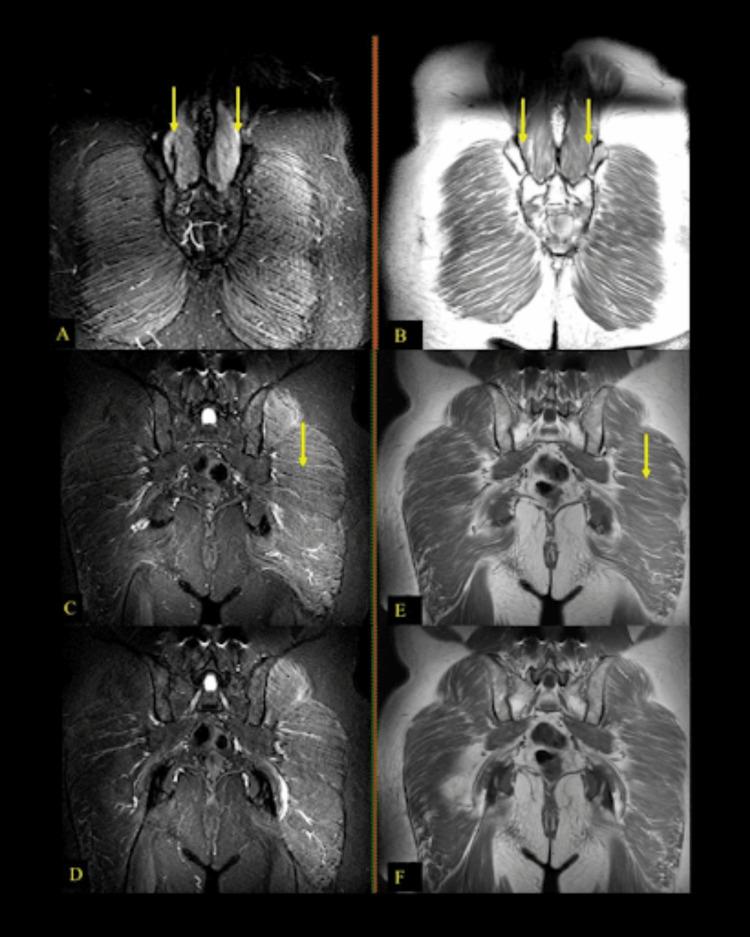

Bruns-Garland Syndrome (BGS), also known as diabetic lumbosacral radiculoplexus neuropathy (DLRPN) or diabetic amyotrophy, is a rare diabetic complication causing progressive muscle weakness, neuropathic pain, and functional impairment. It primarily affects individuals with long-standing type II diabetes, with an underlying mechanism of microvasculitis-induced ischemic injury to the lumbosacral plexus, leading to axonal loss and neurogenic atrophy. We present the case of a 73-year-old physician with type II diabetes who developed progressive thigh weakness and sensory deficits over seven years. Neurological examination revealed amyotrophy, paresis in the pelvic girdle muscles, and absent deep tendon reflexes. Electroneuromyography (ENMG) demonstrated chronic neuro-radiculopathy with significant axonal loss, and MRI showed bilateral muscle atrophy, edema, and fatty replacement. Unlike typical BGS cases, which present acutely with unilateral symptoms, this patient exhibited a chronic, bilaterally progressive form, highlighting diagnostic challenges. Differential diagnoses included chronic inflammatory demyelinating polyradiculoneuropathy, lumbar spinal stenosis, and neoplastic neuropathies. Management focused on glycemic control, physical therapy, and neuropathic pain management, with consideration of immunomodulatory therapy in severe cases. This case underscores the need for heightened clinical awareness of atypical BGS presentations and the role of electrodiagnostic and imaging studies in distinguishing it from other neuropathies. Early recognition and comprehensive management are crucial to improving outcomes and preventing further functional decline.

布伦斯-加兰综合征(BGS),也称为糖尿病性腰骶神经根丛神经病(DLRPN)或糖尿病性肌萎缩,是一种罕见的糖尿病并发症,可导致进行性肌肉无力、神经性疼痛和功能障碍。它主要影响患有长期II型糖尿病的个体,其潜在机制是微血管炎引起的腰骶丛缺血性损伤,导致轴突丧失和神经源性萎缩。我们报告了一例73岁的II型糖尿病医生的病例,该患者在7年中出现了进行性大腿无力和感觉障碍。神经系统检查发现肌萎缩、骨盆带肌肉轻瘫以及腱反射消失。肌电图(ENMG)显示为慢性神经根病,伴有明显的轴突丧失,MRI显示双侧肌肉萎缩、水肿和脂肪替代。与典型的BGS病例不同,典型病例急性出现单侧症状,而该患者表现为慢性、双侧进行性形式,突出了诊断挑战。鉴别诊断包括慢性炎症性脱髓鞘性多发性神经根神经病、腰椎管狭窄和肿瘤性神经病。治疗重点是血糖控制、物理治疗和神经性疼痛管理,严重病例考虑免疫调节治疗。该病例强调了提高对非典型BGS表现的临床认识以及电诊断和影像学研究在将其与其他神经病区分开来方面的作用的必要性。早期识别和综合管理对于改善预后和防止进一步功能衰退至关重要。